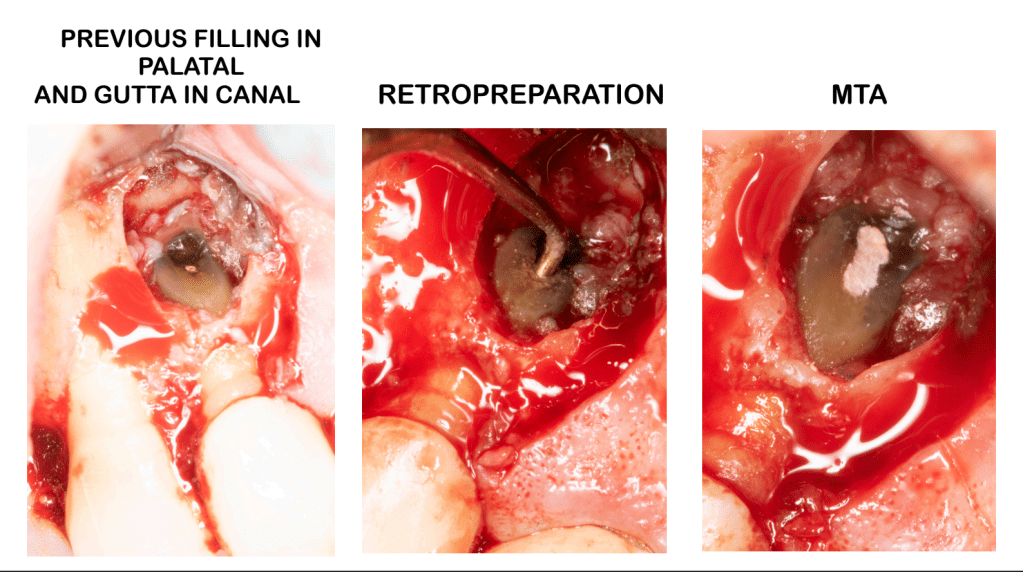

Reimplante, istmo apical, curación cortical palatina 1 año